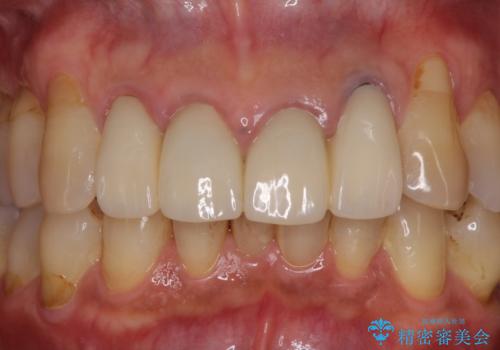

- 昨年治療した前歯の根尖部に痛みを感じ、ラバーダムや顕微鏡を用いた根管治療を希望されて、転院された患者様です。

前医にて神経を取り除いた処置を行った際、ラバーダムが使用されなかったとのことで転院されてきました。

根管治療を実施した後、オールセラミッククラウンに補綴することとしました。

前歯のセラミッククラウンを装着したばかりであったので、根管治療のためにクラウンを壊さなければならないことを残念に思っていらっしゃいました。

しかし、根管治療後はすぐに痛みがひき、治療を受けられて良かったとのことでした。